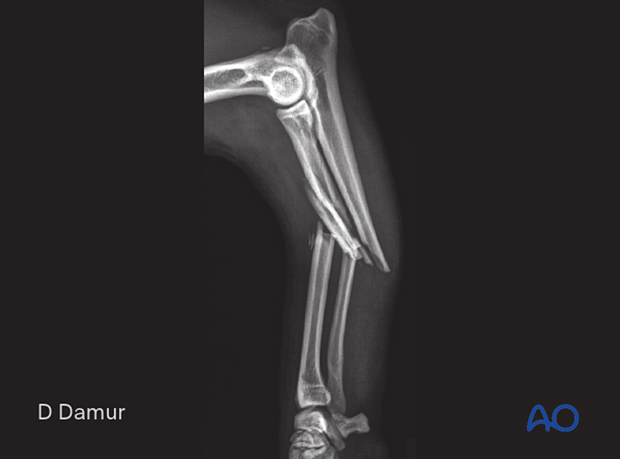

Patient presented with a 22-B3 fracture

22-B3 Wedge fracture of the proximal zone of the diaphyseal radius with multifragmentary ulnar fracture: